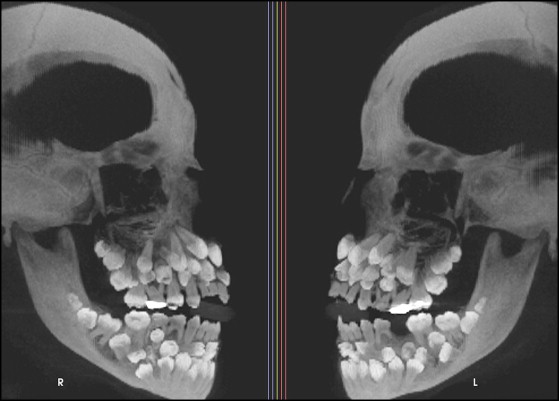

Qua khám trong miệng, các bác sĩ ghi nhận chỉ có 5 răng vĩnh viễn đã mọc. Trong khi đó, các răng sữa vẫn còn tồn tại khá nhiều. Nhằm đánh giá toàn diện hơn tình trạng răng miệng của bệnh nhi, các bác sĩ đã chỉ định chụp phim toàn cảnh và phim sọ nghiêng. Kết quả phim cho thấy một bất thường nghiêm trọng: sự hiện diện của rất nhiều răng thừa.

Hình chụp X-quang của bệnh nhi

Cụ thể, kết quả chụp đã cho thấy bệnh nhân có tổng cộng 81 chiếc răng, bao gồm: 18 răng sữa, 32 răng vĩnh viễn và 31 răng thừa. Các hình ảnh cũng cho thấy nhiều răng có hình thể bất thường khiến việc phân biệt giữa răng thường và răng thừa trở nên vô cùng khó khăn.